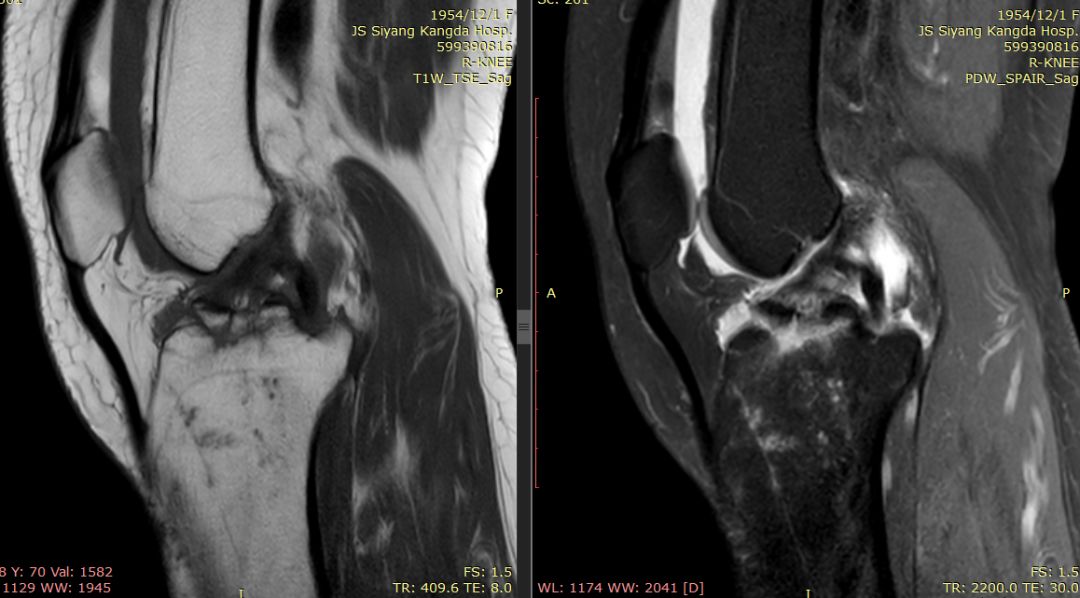

下图横断面的标线标记的是左下图,为外侧半月板的桶柄样撕裂移位

下图标记的是外侧半月板的撕裂

下图示外侧副韧带损伤 腘肌腱损伤 髂胫束连续

内侧副韧带损伤

膝后肌群损伤